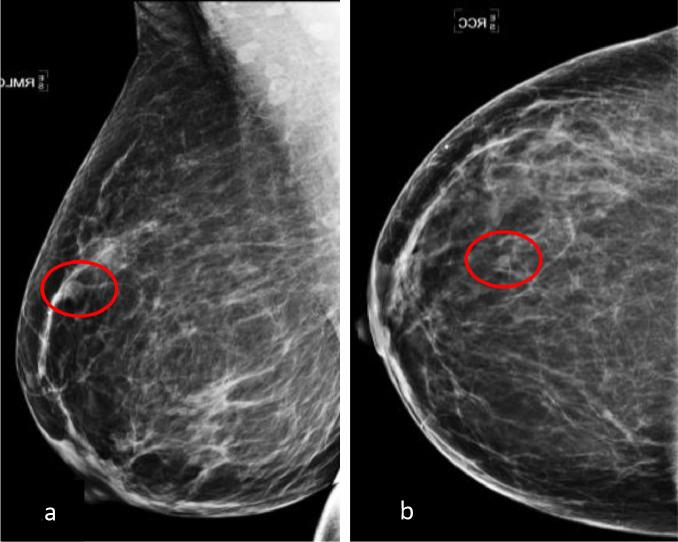

Adenoid cystic carcinoma is a rare form of breast cancer accounting for 0.1%-1.0% of all mammary malignancies. It is characterized by an indolent clinical course and favorable prognosis, contrary to other breast cancers. Diagnostic mammogram and breast ultrasound play a pivotal role in the early detection and diagnosis of breast adenoid cystic carcinoma. Treatment may consist of lumpectomy and radiation therapy vs mastectomy alone. Even though rare, late disease recurrence and metastasis has been reported in the literature thus long-term surveillance is of utmost importance for these patients. We will review the literature and discuss the case of a 52-year-old female who presented with a palpable lump of the right breast, which was pathologically proven to be adenoid cystic carcinoma of the breast.

腺样囊性癌是一种罕见的乳腺癌类型,占所有乳腺恶性肿瘤的0.1%-1.0%。与其他乳腺癌不同,其临床病程进展缓慢,预后良好。诊断性乳房X光检查和乳房超声在乳腺腺样囊性癌的早期检测和诊断中起着关键作用。治疗方法包括肿块切除术加放射治疗或单纯乳房切除术。尽管罕见,但文献中已有晚期疾病复发和转移的报道,因此对这些患者进行长期监测至关重要。我们将回顾相关文献,并讨论一名52岁女性的病例,该患者右乳出现可触及肿块,病理证实为乳腺腺样囊性癌。